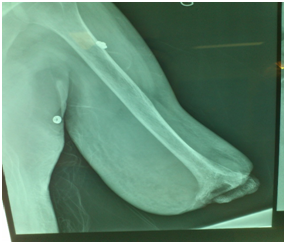

Mr M.E., 38 years old, right-handed, unemployed, known as a drug addict using cocaine by injection, on treatment but poorly monitored. In his background in addition to various infectious episodes, there is essentially this notion of confusion with dysphasia but investigations have not been pushed, was it a transient stroke? He consulted at the emergency for spontaneous loss of his forearm (Figure 1). The patient said it began few months ago when necrotic areas started to appear on his forearm. Each time he consulted a doctor, an antibiotic treatment was prescribed but no improvement was noticed. Worse, neurological disorders started to manifest on his hand with a sphacelus aspect which kept on increasing. For him, that was what motivated him to check it again. A topical antibiotic treatment was prescribed. Noted that the patient’s discourse was inconsistent and seem absurd. Letting things evolve, the eve of his emergency department visit, wanting to wash, his forearm broke away making surgical disarticulation at his elbow. On examination we were amazed by the calm of the patient who arrived with his forearm which looked like mummified in a bag. The spontaneous amputation was done at the elbow joint with exposure of the distal hummers (Figure 2). The x-ray examination did not show signs of osteitis (Figure 3). After assessment, the patient was taken to the operating room where we conducted further amputation stump with regularization (Figure 4).

Figure 3 X-ray examination.